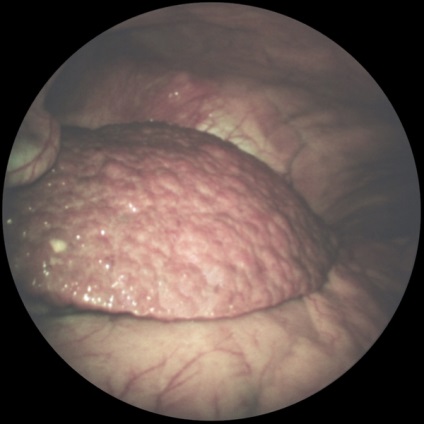

Az első lépés a bevezetése pneumoperitoneum L. a. A hasat kilyukadt egy speciális tű (a tű típusától Leriche) a bal alsó pont nyomkövetés (ábra. 1). A hasüreget adjuk 3000-4000 cm3 levegőt. dinitrogén-oxid vagy szén-monoxid. Attól függően, hogy a célkitűzések a tanulmány beadásra laparoszkópon egyik kiválasztott pontok szerinti rendszer felkutatása gyakran fent és bal oldalán a köldök. Szike, hogy egy bőr bemetszést 1 cm. Boncolással a bőr alatti szövet, és a fascia a rectus abdominis. Ezután, a hüvely trokár szúrja a hasfal, a trokár eltávolítják, és ezen keresztül a hüvely kerülnek bevezetésre laparoszkópot. Ellenőrzés a has szakaszosan végezzük jobbról balra, megtekintésekor a jobb oldali csatorna, a máj, obstruktív és mellékvese térben szubdiafragmatikus helyet. bal oldalsó csatornát medencét. Meg lehet változtatni a helyzetét a beteg részletesebb ellenőrzést. A színe, jellege a felület, az alak a test átfedések, hiszen folyadékgyülem lehet beállítani lézió jellege: májzsugor (2A ábra.) Metasztatikus (2b ábra.), Heveny gyulladás (2. ábra, d.) nekrotikus folyamat (ábra. 2, stb), stb A diagnózis megerősítésére biopszia (általában egy defekt). Széles körben használják különböző orvosi eljárásokban L. hasi vízelvezető (3A.), Mikroholetsistostomiya (ábra. 3b), és mások. Lezárását követően laparoskipii laparoskona és extrahálás a hasüregből a gáz eltávolítása után a bőrön sebet lezárjuk 1- 2 öltés.

Ábra. 2a). Laparoszkópos képet bizonyos betegségek és patológiás állapotok a hasüreg - SKD cirrhosis.